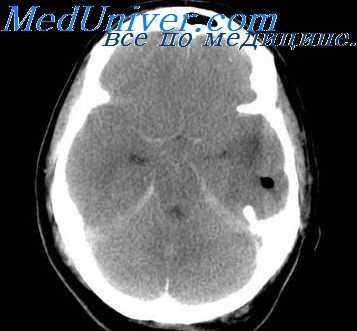

- КТ или МРТ головного мозга. Исследования дают возможность четко визуализировать локализацию абсцессов или очагового энцефалита, определить их размеры, выявить перифокальный отек, дислокацию и деформацию желудочков мозга. Контрастные методики показаны при подозрении на тромбоз кавернозного или сигмовидного синуса.